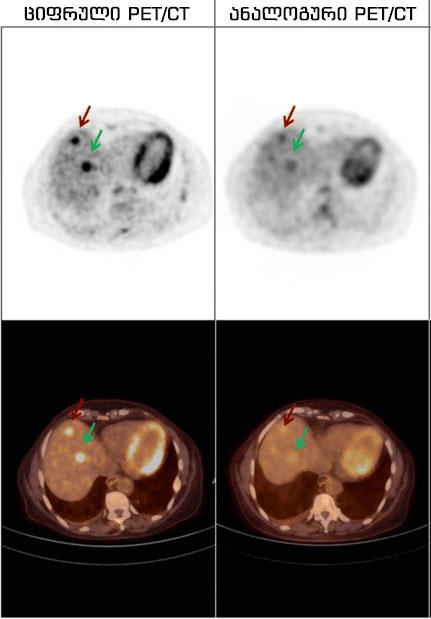

Philips Vereos digital PET/CT აპარატმა გლობალურ ბაზარზე აღიარება გამოჩენისთანავე მოიპოვა. იგი მსოფლიოში პირველი და ერთადერთი სრულად ციფრული სკანერია. სხვა ანალოგურ აპარატებთან შედარებით კი, ციფრული PET/CT:

ძველი თაობის , „ანალოგური“ დანადგარებისგან განსხვავებით, მას შეუძლია მილიმეტრული სიზუსტით, ადამიანის სხეულის ნებისმიერ წერტილში არსებული ისეთი მცირე ზომის კიბოს უჯრედისა თუ გავრცელებული მეტასტაზების დანახვა და ზუსტი მდებარეობის განსაზღვრა, რომლებიც არ ჩანს კომპიუტერული ტომოგრაფიის, მაგნიტურ-რეზონანსული და სხვა რადიოლოგიური გამოკვლევების დროს. თავად, კომპანია Philips-ის შეფასებით, ეს არის აპარატი, რომლის გამჭრიახ თვალსაც მილიმეტრული ზომის წარმონაქმნიც კი არ გამოეპარება! ასევე, აღსანიშნავია, რომ პეტ/კტ კვლევა, ონკოლოგიურ შემთხვევათა 36%-ში, მკურნალობის ტაქტიკას ცვლის!